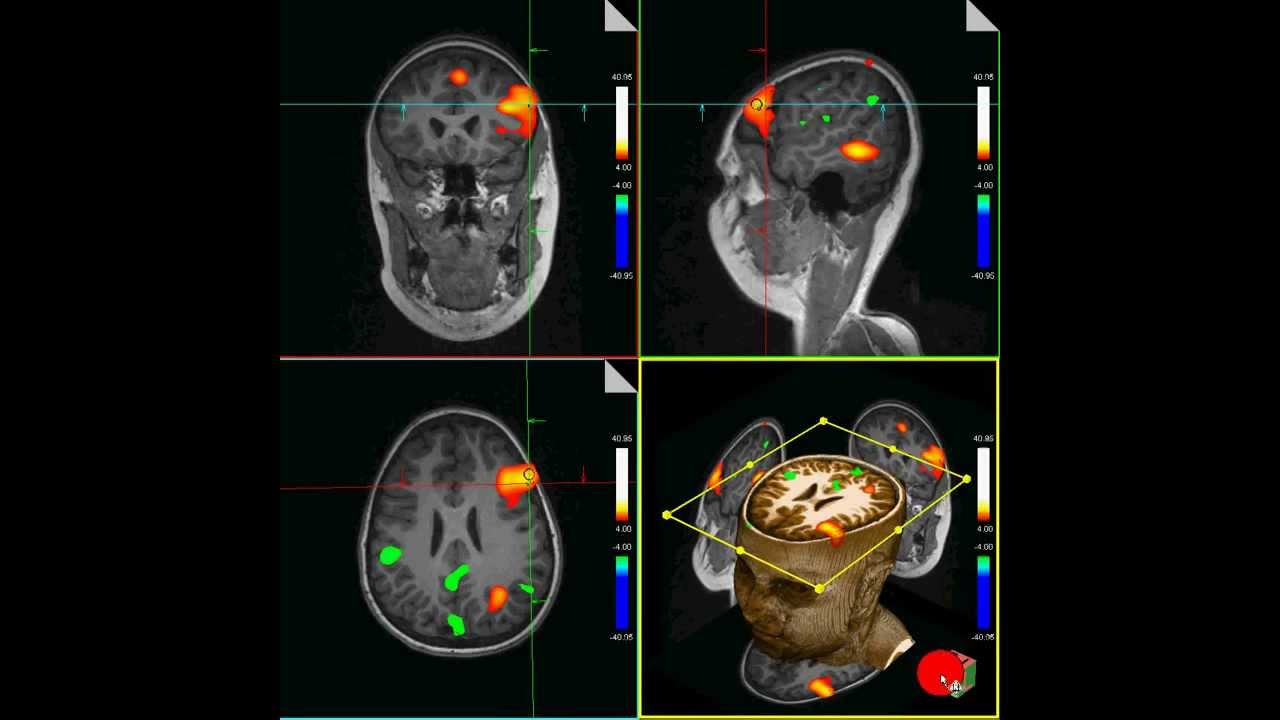

Функциональная магнитно-резонансная томография

Аппарат ФМРТ (функциональная магнитно-резонансная томография) может заглянуть внутрь мозга при гораздо большем пространственном и временном разрешении, чтобы наблюдать, как мозг выполняет задачи в реальном времени. ФМРТ работает, измеряя магнетизм железа в гемоглобине крови, что показывает соотношение богатой кислородом и бедной кислородом крови в разных областях мозга. В областях активности приток насыщенной кислородом крови больше (из-за расширения кровеносных сосудов).

Установка ФМРТ была одним из самых значимых диагностических достижений в неврологии в 1990-е годы. Она дает ученым возможность увидеть, какие области мозга возбуждены (освещены), когда мозг выполняет различные действия, например, погружен в глубокую задумчивость или занят так называемой «бездумной болтовней», что происходит в минуты глубокого религиозного экстаза, созерцания вдохновенного произведения искусства или зарождающейся влюбленности.

Один из авторов этой книги, Рей, сделал ФМРТ как часть тематической статьи в журнале Inc. в 2002 году. На снимке видно, как разные области мозга активизировались, когда его просили перестать думать о будничных вещах и перейти к решению умственной задачи.